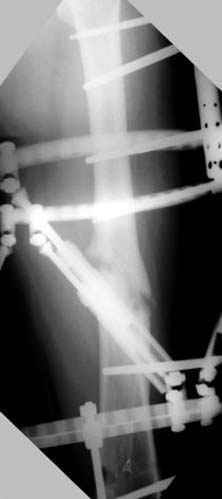

На рисунке N1 предоперационный план лечения ложного сустава шейки бедра- линия ложного сустава, угол и направление введения импланта, клиновидная остеотомия в градусах и миллиметрах, второй снимок после коррекции, расчет, на сколько удлиняется конечность и размеры импланта;

N3 рисунок окончательный снимок, после операции моя рентгенограмма должен выглядеть примерно как эта картина. На N4 снимке клин перед удалением; N5 послеоперации 3 нед.; N6 окончательная рентгенограмма.

Отправитель: Djoldas Kuldjanov 23 Ноябрь 2004, 18:21

пластическая модель; и коррекция бедра аппаратом Илизарова.